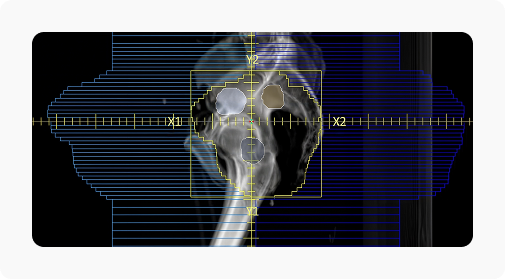

LinaTech VenusX — это линейный ускоритель с ортогональным многослойным многолепестковым коллиматором (МЛК). Коллиматор адаптирует пучок под сложную форму мишени, равномерно распределяет дозу облучения и снижает лучевую нагрузку на здоровые ткани и органы риска. Линейный ускоритель размещается в компактном каньоне от кобальтовых аппаратов.

ИИ совмещает kV CBCT, MV EPID и BPS изображения, чтобы повысить точность облучения.

Множество мишеней

Ортогональный многослойный МЛК облучает несколько мишеней сложной формы одновременно.

Низкий уровень утечки

Синхронное движение 102 пар лепестков МЛК сокращает время лечения и уровень утечки.

| Тип коллиматора | Многолепестковый , Многослойный , Ортогональный |

| Количество слоев коллиматора [шт] | 2 |

| Количество лепестков коллиматора [шт] | 204 |

| Минимальная ширина лепестка на изоцентре [мм] | 4 |

| Максимальная скорость движения лепестков на изоцентре [см/сек] | 7 |